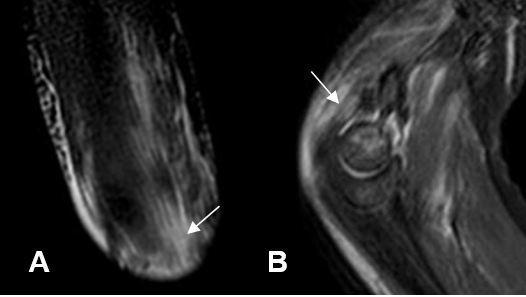

Fig 43 C. Bursitis del tríceps.

A: RM STIR sagital y B: RM axial en T2. Imagen líquida, en la región posterior del codo, (Flecha delgada) en relación con el tendón del tríceps normal. (Flecha gruesa).